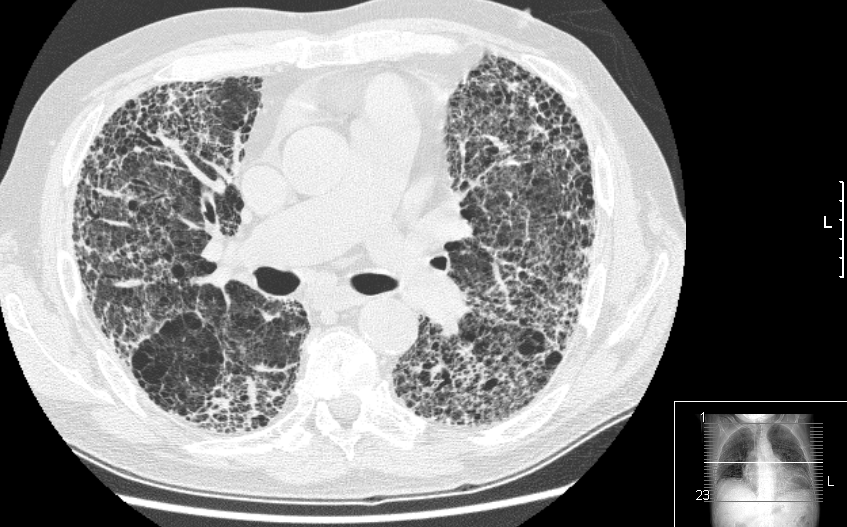

폐섬유증은 폐 조직이 흉터 조직으로 대체되어 폐 기능이 저하되는 질환이다. 주요 증상으로는 호흡 곤란, 만성 기침, 피로감, 흉통, 체중 감소 등이 나타나며, 흉부 엑스레이나 고해상도 CT를 통해 진단한다. 폐섬유증은 특발성 또는 다른 질병의 합병증으로 발생할 수 있으며, 석면 노출, 자가면역 질환, 특정 약물 등이 원인이 될 수 있다. 현재 완치법은 없으며, 치료는 증상 완화와 질병 진행 억제에 초점을 맞춘다. 약물 치료, 산소 치료, 폐 이식 등이 사용되며, 연구를 통해 새로운 치료법 개발이 진행 중이다.

폐섬유증의 주요 증상은 호흡곤란(특히 운동 시), 만성적인 마른 기침, 피로감, 가슴 통증을 동반한 답답함, 식욕 부진 및 급격한 체중 감소 등이다.[46][1] 이러한 증상은 과로와 함께 진행되며, 청진 시 폐 기저부에서 미세한 흡기 시 딱딱거리는 소리(수포음)가 들리기도 한다. 흉부 엑스레이는 정상 또는 비정상으로 나타날 수 있지만, 고해상도 CT에서는 비정상적인 폐의 모습을 확인할 수 있다.[47][3]

호흡곤란(특히 운동 시 악화)[46][1], 만성적인 마른 기침[46][1], 피로감 및 쇠약[46][1], 흉부 불편감, 흉통[46][1], 식욕 부진 및 급격한 체중 감소[46][1] 등의 증상이 주로 나타난다. 폐섬유증은 과로와 함께 진행되는 호흡곤란 증상으로 진찰될 수 있다. 때때로 청진 시 폐 기저부에서 미세한 흡기의 딱딱한 소리가 들릴 수 있다. 흉부 엑스레이는 정상 또는 비정상으로 나타날 수 있지만 고해상도 CT에서는 비정상적인 폐의 모습을 볼 수 있다.[47][3]2. 2. 진찰 소견

폐섬유증은 활동 시 진행성 호흡곤란으로 진찰될 수 있다. 때때로 청진 시 폐 기저부에서 미세한 흡기성 수포음(딱딱거리는 소리)이 들릴 수 있다.[47][3] 흉부 엑스레이는 정상일 수 있지만, 고해상도 CT는 종종 이상 소견을 보인다.[3]3. 원인